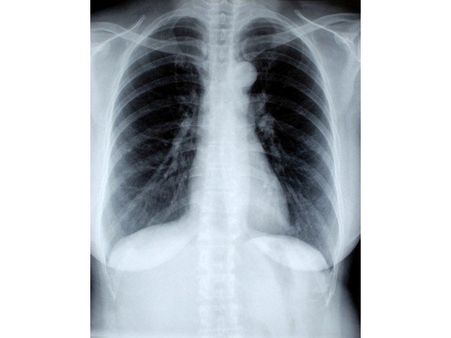

Diagnosis Of Walking Pneumonia

- X-ray: To view the spread of the infection in the lungs and also to rule out other conditions.